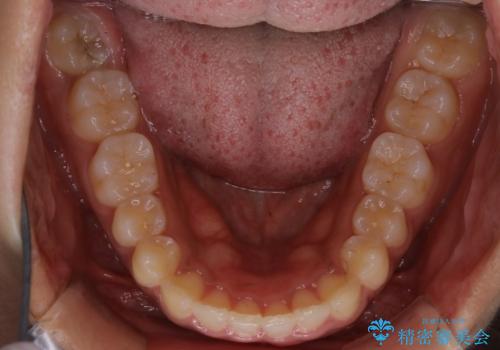

インビザライン矯正 歯を抜かずに出っ歯を改善!

- 出っ歯と前歯の隙間が空いていることを気にされて来院されました。

また、自然な感じで口元を下げていとのことでした。

奥歯のかみ合わせが問題なかったため、上顎の前歯の隙間を閉じるとともに、上顎の歯の側面を削ることをメインにして、出っ歯を改善する治療計画としました。

上顎の歯の傾きを変えるうえで、下顎の歯とのバランスのことも考え、下顎の歯の側面も削ることを加えています。

また、今回は口元を変えたい中に、劇的な変化は避けたいとのことだったので、抜歯をしない計画としています。

抜歯をしない場合、口元の変化は感じにくいですが、前歯の傾きが変わることで、口の閉じやすさは感じていただけたとのことです。

症例にもよりますが、本症例は奥歯のかみ合わせに問題がなかったので歯の側面を削ることメインに、前歯の傾きを改善することができました。

抜歯を行う場合や抜歯をしなくても奥歯の位置をずらす場合は、治療期間が長期化することが多いですが、今回は歯を削ることで改善できたため、短期間で治療を完了することができました。